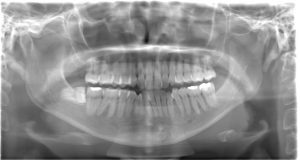

レントゲン写真

親知らずが真横を向き、手前の歯にぶつかっています。

その部分に汚れが溜まりやすくなっていますが、歯ブラシではなかなか落とすことが難しいと思われます。

しかし、下図の赤い線で囲まれた部分は顎の中に通る神経や血管がある空洞です。

レントゲン上ではこの部分と親知らずの根の先が触れているように見えます。

この神経は唇や顎の感覚を司る神経です。

抜歯の際に無理な力でこの神経を圧迫してしまうと、唇や顎の一部に麻痺がでてしまう可能性があるため注意が必要です。